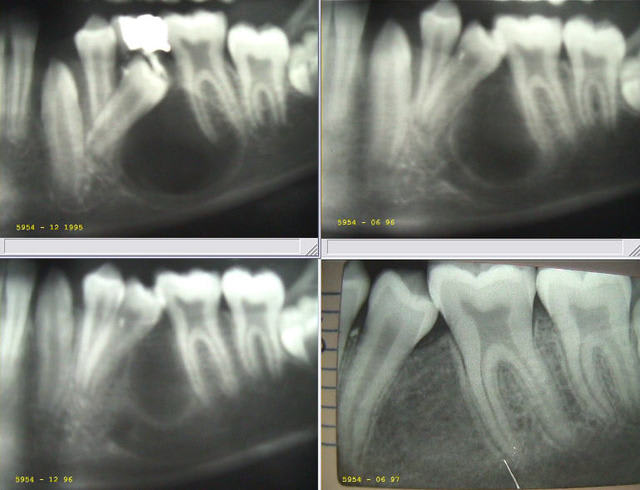

J'avais oublié de vous donner la suite des deux autres cas, la voici :

Image4 meixqh - Eugenol

Image5 vwswdj - Eugenol

Image odged8 - Eugenol

Je reprends les diapos de l’époque, les numérise et vous les présente incessamment..